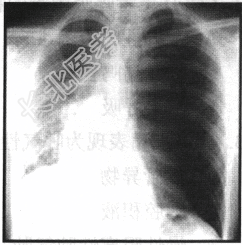

- 单项选择题男性患者,22岁。左侧胸壁刺伤3小时, 呼吸窘迫,结合以下胸片检查该患者最可能的诊断( )。

A、气胸

B、纵隔气肿

C、胸腔积液

D、肺挫伤

E、肺气肿